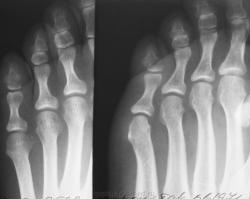

Продолжение.

Данные за перелом сомнительные. Такая скиалогическая картина встречается часто, именно в V пальце стопы.

Если присутствует факт травмы и в связи с тем, что я не знаю о том, что такая картина частая, я бы поставил перелом.... для подстраховки выполнил бы снимок второй стопы.

Считаю, перелома нет!